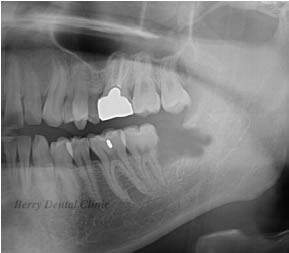

親知らずを1、2、3、と番号順にカットしていきます。

順番に取り除いていきます。

この画像では2の部分を取り除きました。